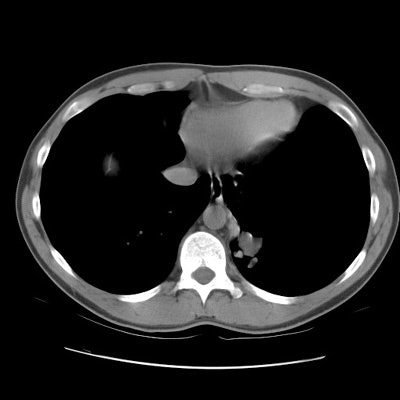

The patient below presented for evaluation of an abnormal CXR which demonstrated a left retrocardiac mass. (Click image to enlarge)

CT scan revealed a soft tissue mass in the left posterior-medial lung which had a branching tubular appearance. Some associated para-emphysematous changes were noted. (Click images to enlarge)